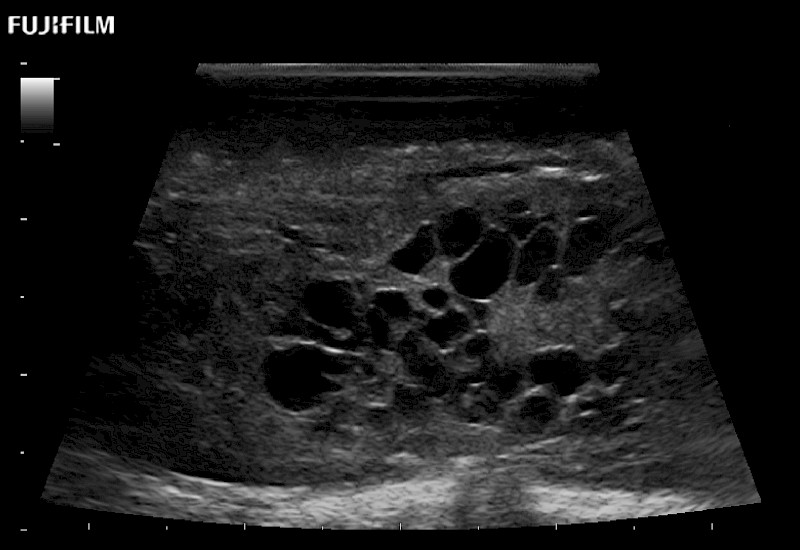

Exclusive 10mm side‐fire linear array transducer with 2.87mm diameter is ideal for real‐time visualization through and behind structures and instant, scalable definition of anatomy and vascularity including the ability to delineate and define tumor margins.

Guidance is the fundamental purpose for all of our surgical ultrasound technology. Fujifilm Healthcare is committed to designing tools that help neurosurgeons navigate inside the human body and provide the necessary information to immediately make critical surgical decisions.